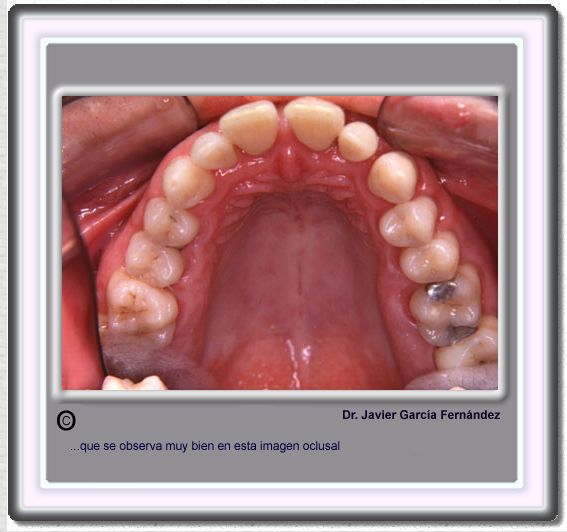

image 672